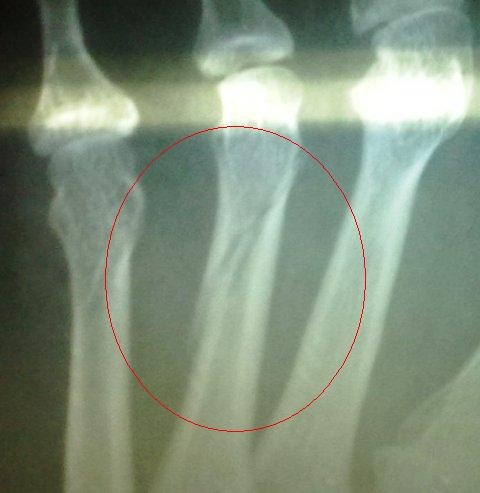

Dan inilah hasilnya dari terpelecok apabila memijak tepi tilam.....lepas ni mokde tak boleh banyak berjalan...kene banyak berehat kata doktor....Dah banyak kali kami menyuruh mokde pergi check-up atau mengurut...mokde kata "takpelah,lelama ok la tuh"...degil atau liat jugak mokde ni..

Semasa check-up,dr meng x-ray kaki mokde...dan hasilnya..kaki mokde patah tapi tulang yang patah tidak putus...semoga Allah melindungi keluarga kami..